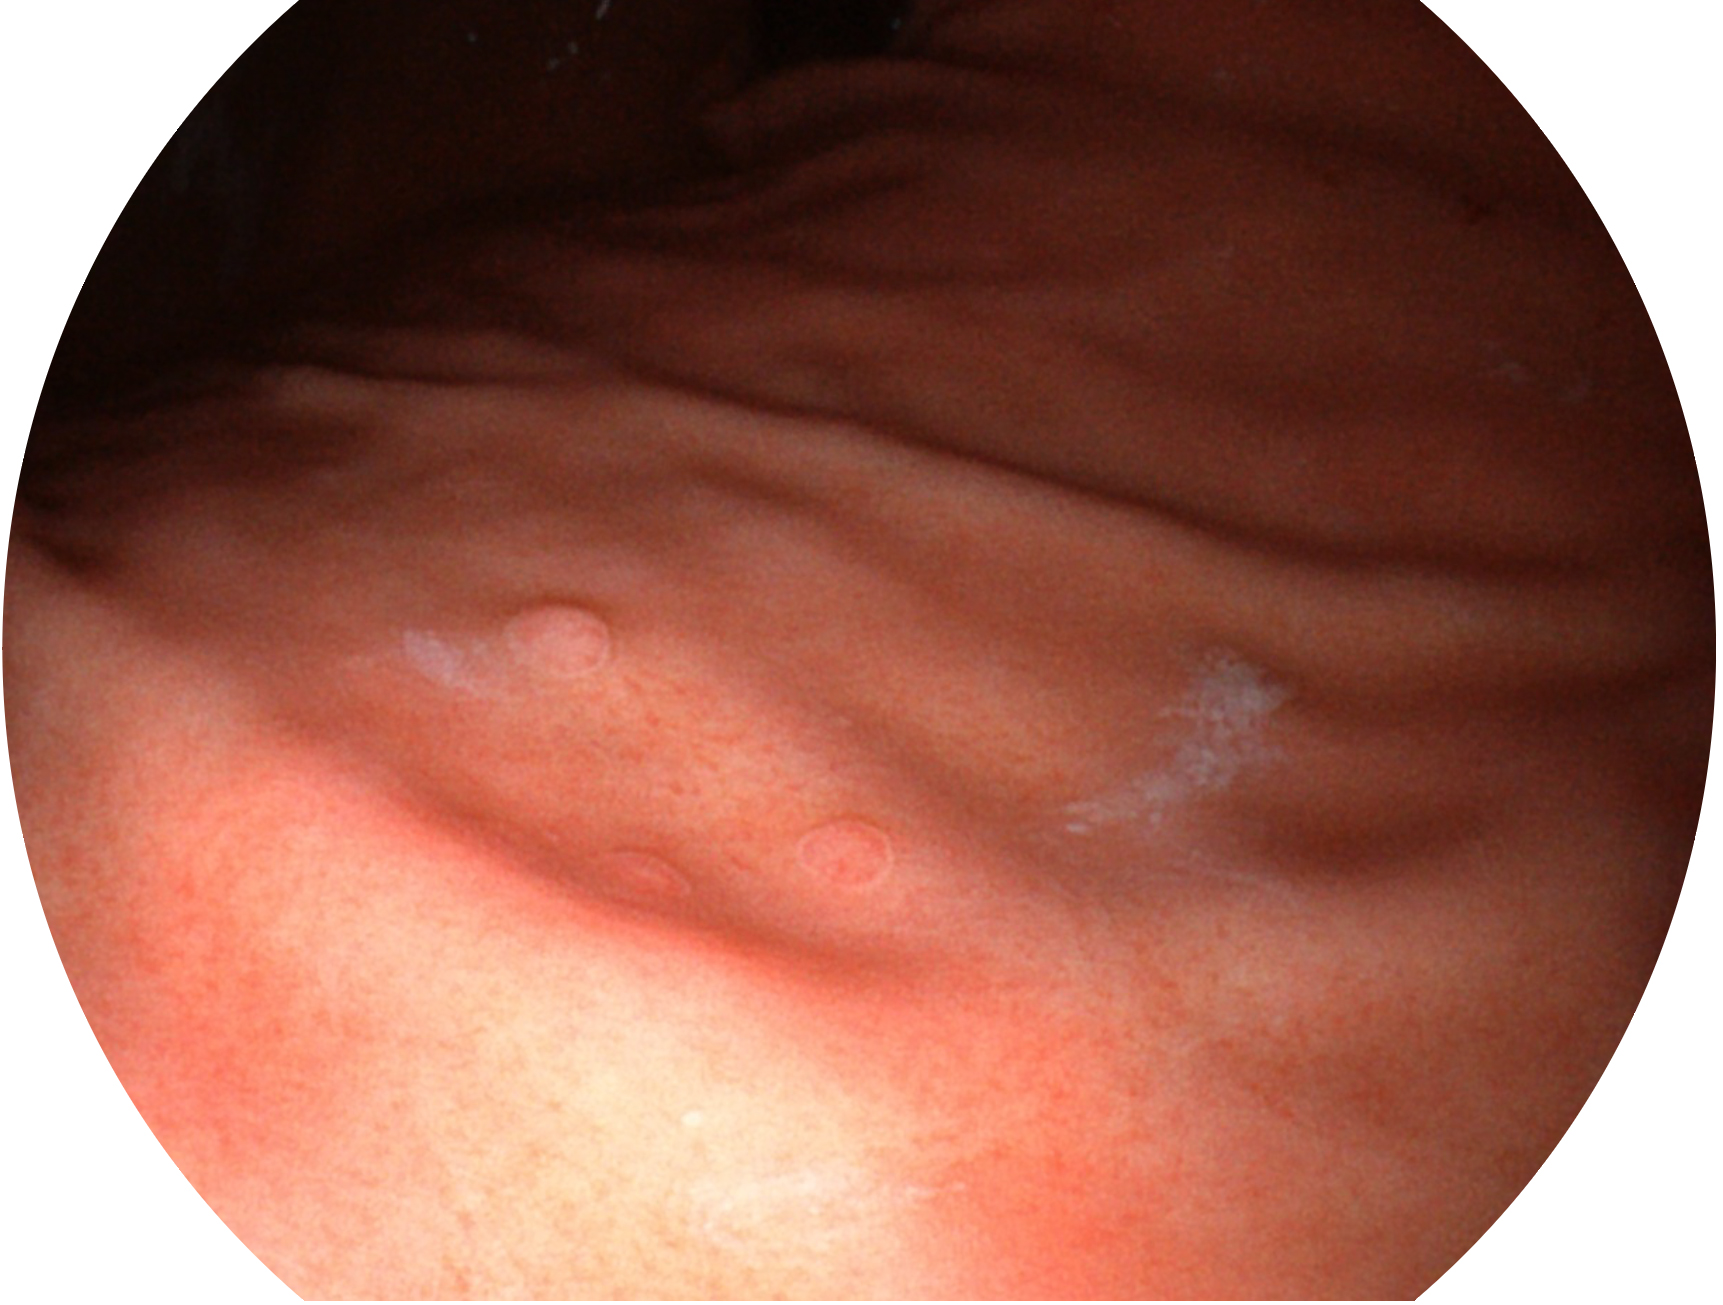

云顶集团官网新开发的内镜染色技术,主要是基于多波长LED 光源的开发,VLS-55Q 四波长LED 光源是由四个不同颜色的LED光按照相应照明模式所规定的特定发光比例进行合束后形成,合束后形成的照明光的光谱由红光、绿光、蓝光及蓝紫光这四个不同的波段范围构成。具有更高光谱自由度,通过光谱比例的控制,实现了聚谱成像技术,英文全称为“Spectral Focused Imaging, SFI”,缩写为“SFI”和光电复合染色成像技术,英文全称为“Versatile Intelligent Staining Technology, VIST”,缩写为“VIST”。